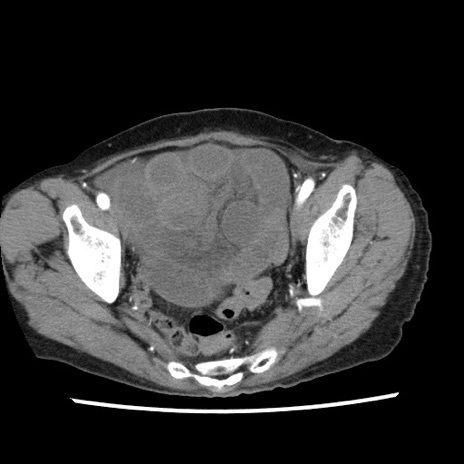

症例1(横断像)

【症例】80歳代女性

【主訴】腹痛

【現病歴】8時間前から腹痛あり来院。

【既往歴】糖尿病、脂質異常症、子宮体癌にて子宮全摘術

【身体所見】意識清明・会話良好だが腹痛で苦悶様、全腹部にわたって反跳痛と圧痛あり

【データ】WBC 13600、CRP 0.14、LDH 224、CK 90